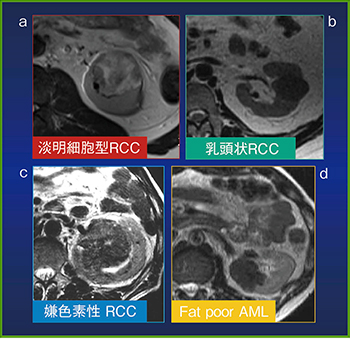

また,腎腫瘤のタイプは血流でも鑑別できるが,MRIのT2強調画像における信号の違いも役に立つ(図2)。特に,淡明細胞癌はin phaseに比べてopposed phaseでは低信号となることがある(図3)。

図2 MRIのT2強調画像における腎腫瘤の信号

a:淡明細胞型腎細胞癌は不均一な高信号を示す。

b:乳頭状腎細胞癌は均一な低信号を示す。

c:嫌色素性腎細胞癌は軽度低信号から軽度高信号を示す。

d:脂肪の少ない腎血管筋脂肪腫は筋肉に近い低信号を示す。